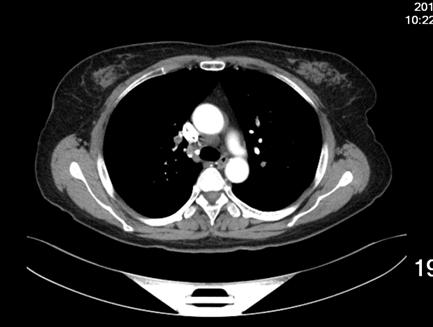

患者女性,52岁,因右膝关节疼痛,活动受限三十年入院。既往无高血压等慢性病史,无静脉血栓栓塞症病史,无慢性静脉瓣功能不全病史。诊断:右膝半月板损伤,骨关节炎。术前排除手术禁忌,于CSEA下行右膝关节镜下探查清理,半月板成形术。手术过程顺利,手术使用止血带,手术时间25分钟,失血约10ml。术后24小时患者下床后出现头晕、头迷、气短、冷汗、扶墙晕倒于墙边,给予心电血氧监护,血压:78/45mmHg,心率:118次/分,指脉血氧饱和度:78%,急检指尖血糖:6.4,血浆D-二聚体:1247ug/L,心肌酶谱及肌钙蛋白未见明显异常,术后2天夜晚再次出现头晕,头迷,气短,冷汗等症状,给予吸氧等治疗后症状缓解,检查肺增强CT(图1),示患者多发肺动脉栓塞,行双下肢静脉彩超检查,示右小腿肌间血栓,左小腿肌间静脉扩张(图2)。术后第3天于局麻下行经皮下腔静脉滤器置入术后,转入呼吸科行继续治疗。

1增强肺动脉CT:多发性肺动脉栓塞。